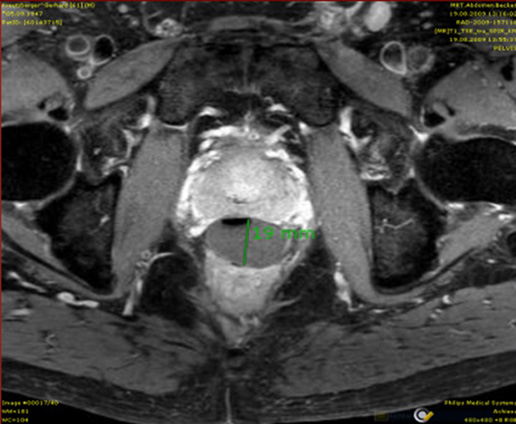

Radiologic image of ventricular histiocytosis on two cases Streszczenie Wstęp: Histiocytoza jest schorzeniem wieloukładowym [1], w którym dochodzi do zaburzenia czynności układu siateczkowo-śródbłonkowego, które prowadzi do ciągłej stymulacji immunologicznej, podziałów i nagromadzenia komórek Langerhansa w różnych narządach. Histiocytoza jest rzadką chorobą występującą najczęściej u dzieci w wieku 1-3 lat [2], nieco częściej u chłopców [3-5]. Przypadek kliniczny: Przedstawiamy obraz radiologiczny histiocytozy z…